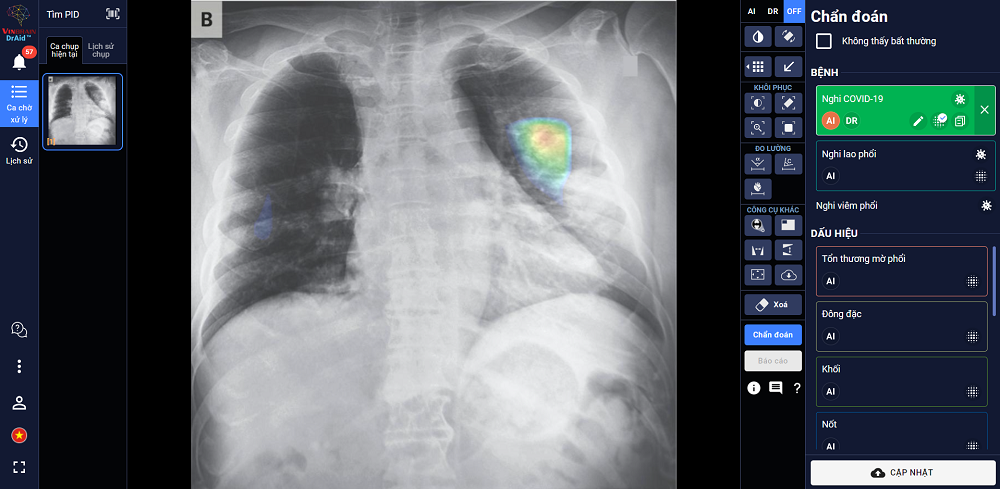

Tài liệu cung cấp thực trạng chẩn đoán lao hiện tại; đồng thời giới thiệu mô hình AI chẩn đoán và tầm soát bệnh lao phiên bản đầu tiên với độ nhạy 86% và độ đặc hiệu lên đến 96,1 %.

Nhằm nâng cao hiệu quả chẩn đoán và điều trị bệnh lao, VinBrain và FIT - Tổ chức phi chính phủ của Đức hoạt động trong lĩnh vực phòng và chống lao đã hợp tác biên soạn và phát hành sách trắng.